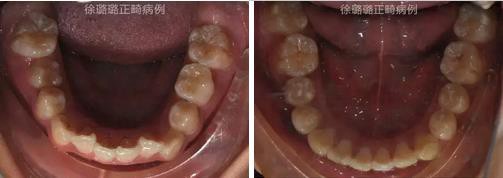

口內(nèi)特征:恒牙早期,雙側(cè)磨牙關(guān)系為輕度遠中關(guān)系,前牙深覆牙合 Ⅱ°,深覆蓋 6mm,上下頜牙弓中線不端正,上頜中線右偏 3mm,上頜前牙唇傾,下頜牙列輕度擁擠,右側(cè)上頜間隙不足,左側(cè)乳尖牙滯留,上頜左側(cè)乳尖牙對刃牙合,上下頜牙弓形態(tài)不對稱。